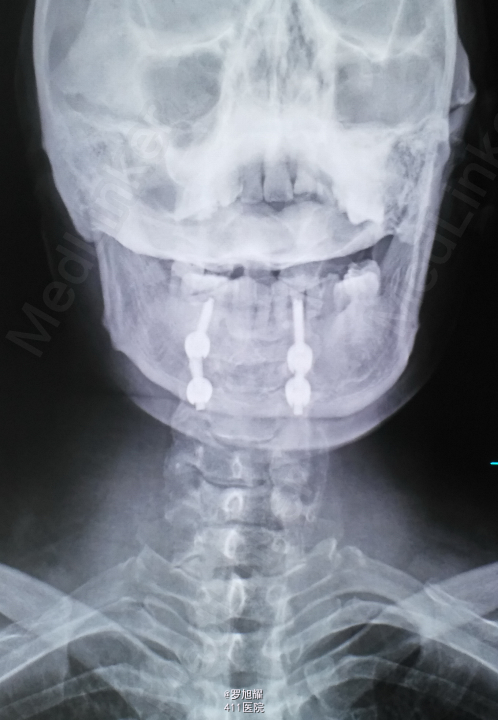

左侧锁骨平面以下痛温觉、位置觉消失,右半身感觉正常。会阴部感觉存在。左侧肢体肌力正常,右侧上下肢肌力0级。右侧腱反射均消失。影像学检查示双侧枢椎椎弓骨折,MRI脂肪抑制成像颈1-2平面脊髓信号略高。

入院立即给与大剂量甲强龙冲击治疗,辅以甘露醇脱水消肿,兰索拉唑保护胃黏膜,腺苷钴胺恩经复营养神经,伤后10天复查MRI脊髓信号增高明显,两周后生命体征稳定,肢体感觉和肌力见部分恢复,行颈2椎弓根螺钉、颈3侧块钉内固定术,因神经压迫不明显未行椎板切除减压。 术后3月骨折线基本消失,患者感觉肌力几乎完全正常,右肩残留疼痛磁共振检查发现肩袖损伤,暂予局封治疗症状缓解。